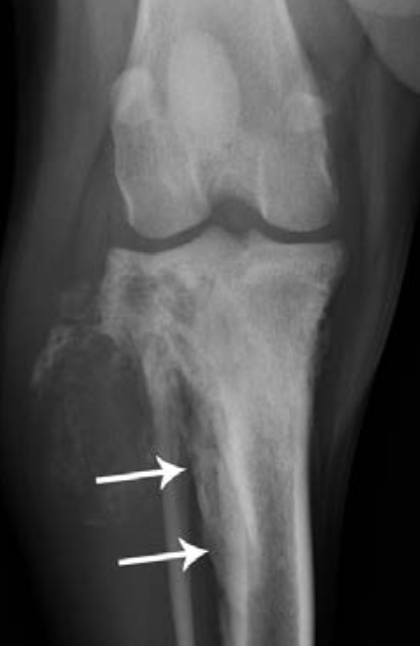

A

Proximal tibial

osteosarcoma with amorphous bone

formation seen lateral to the proximal fibula. A solid periosteal reaction (Codman’s triangle, arrowed) is present on the lateral cortex of the proximal tibial diaphysis.